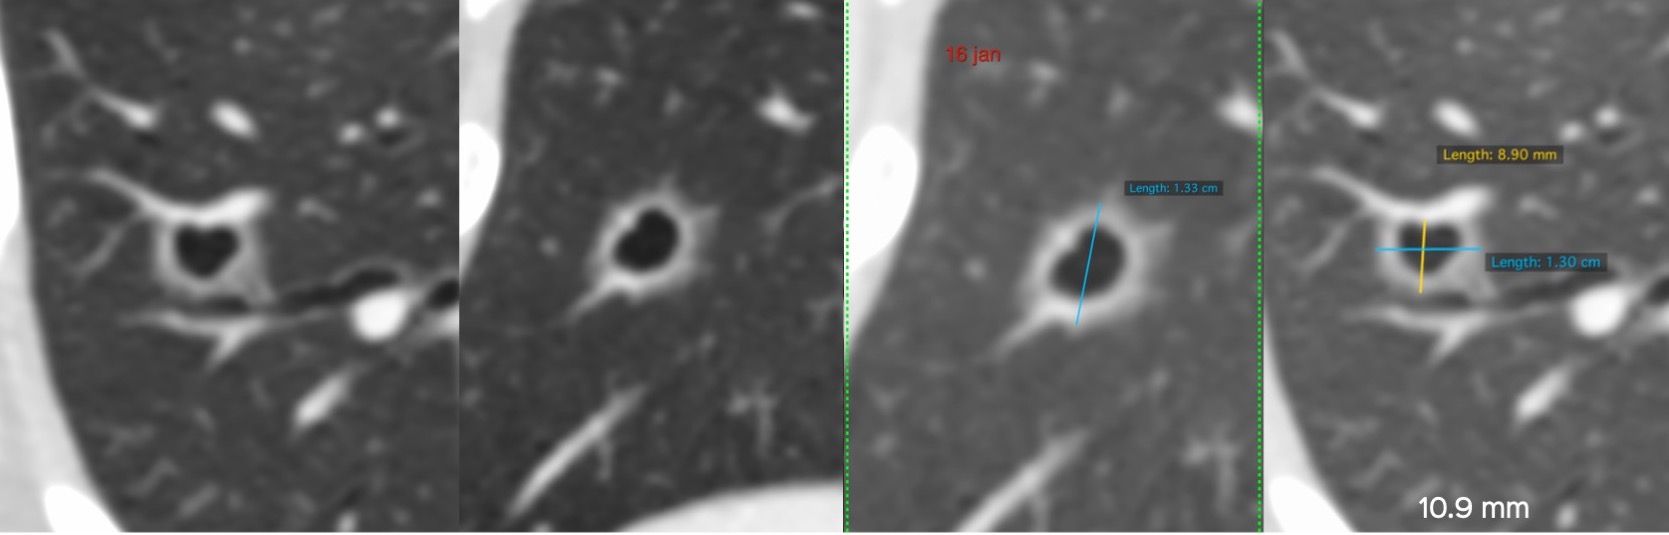

This 55-years old patient operated in the past for carcinoma of the ampulla of Vater presented with an incidental cavitated lung nodule on a CT abdomen in Jan.

In March, the lesion was unchanged in size but the morphology had altered.